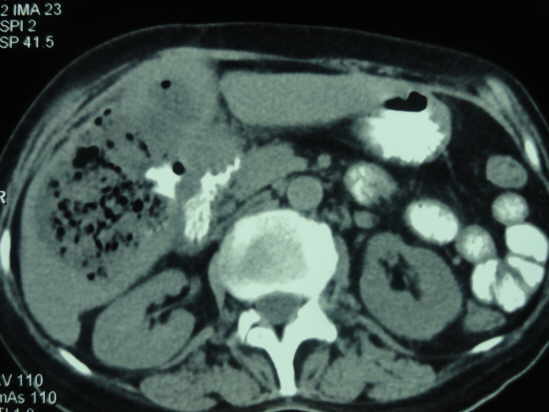

Tomografía Axial Computarizada de Absceso Hepático Amebiano

La sintomatología del absceso hepático amibiano se ha englobado en lo que se denomina la “triada clásica”: hepatomegalia, dolor en hipocondrio derecho y fiebre, asociados a leucocitosis en presencia de neutrofilia y pruebas serológicas para E. histolytica positivas.